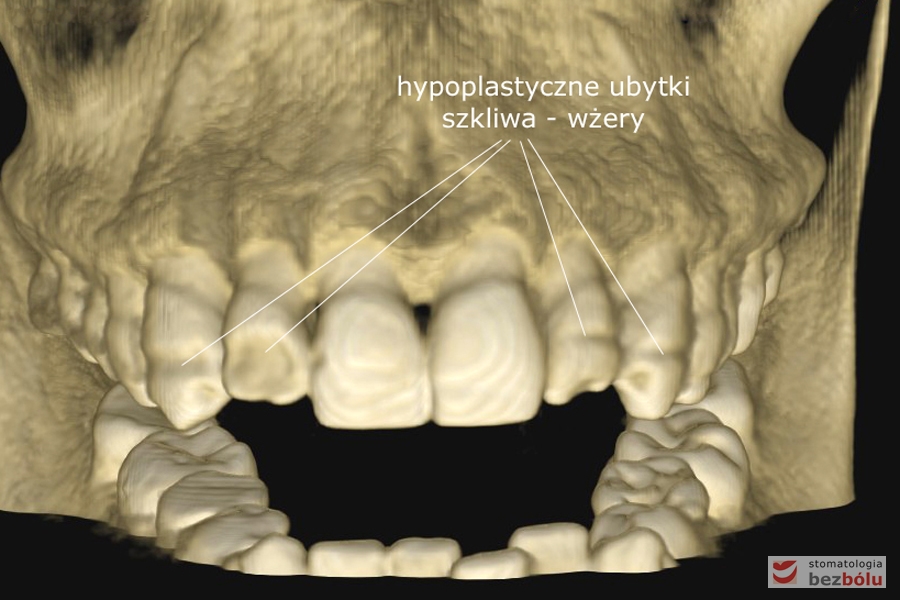

Diagnostyka tomograficzna - wolumetryczna rekonstrukcja układu kostno-zębowego

Diagnostyka tomograficzna – wolumetryczna rekonstrukcja układu kostno-zębowego